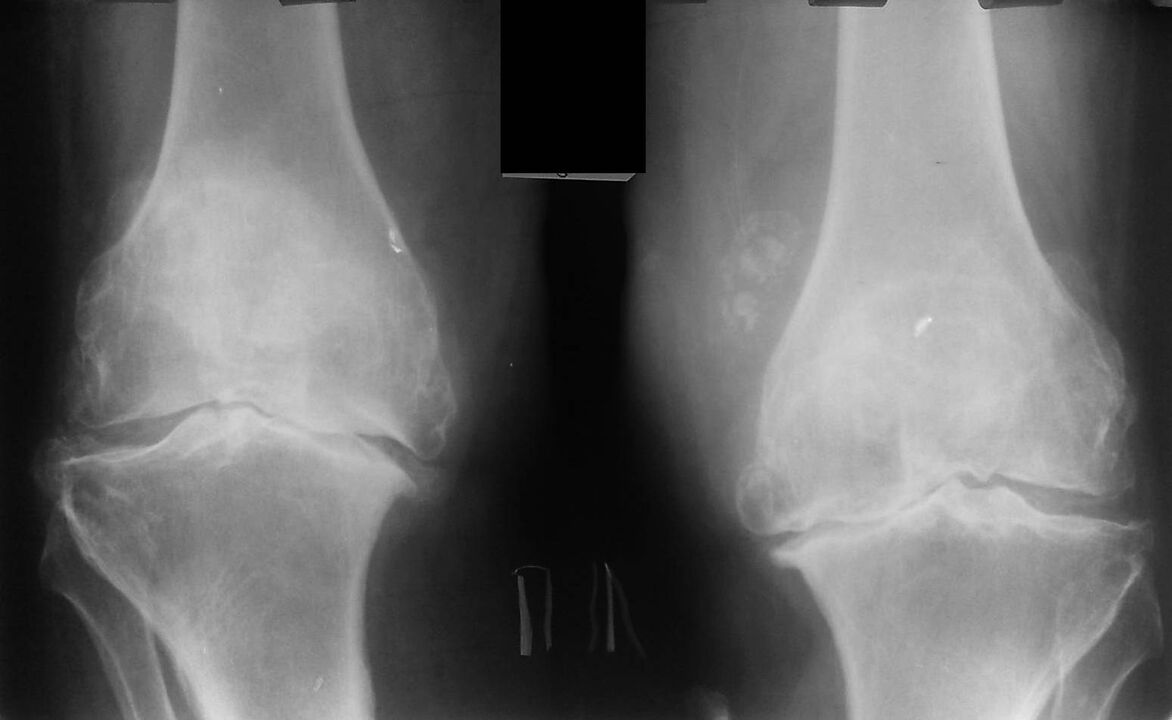

Spray Hondrox artikulazioetako minaren erremedioa da. Droga artritisa, artrosia eta beste gaixotasun artikulatuen tratamenduan eta prebentzioan erabiltzen da. Spray Hondrox konposizio naturala du, efektu antiinflamatorio eta birsortzaile indartsua du, mina eta hantura arintzen ditu. Espainiak Hondrox spray-aren eraginkortasuna aitortu du artikulazioen tratamendurako eta prebentziorako, produktua webgune ofizialean eros daiteke, eta Santa Cruz de La Palma produktua entregatzeko likidazioen artean dago.